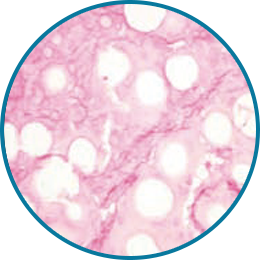

노화가 진행되면 섬유아세포와 콜라겐의 활성과 텐션이 감소되어

탄력 감소, 주름, 피부 색변화, 볼륨 감소 등이 발생됩니다.

섬유아세포와 콜라겐의 활성도와 텐션이 점차 감소됨

탄력감소, 주름증가, 볼륨이 감소된 피부

피부에 주입시켜 섬유아세포의 활성과 텐션을 회복하는 것은 바이오 스티뮬레이터인 레디어스의 가장 큰 특징입니다.